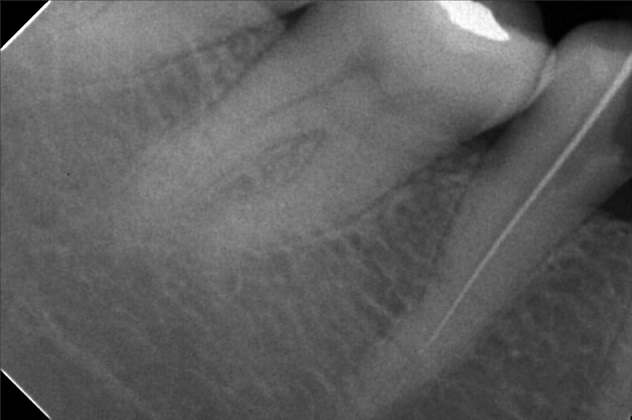

- Procedure

- File

- sevilla.jpg